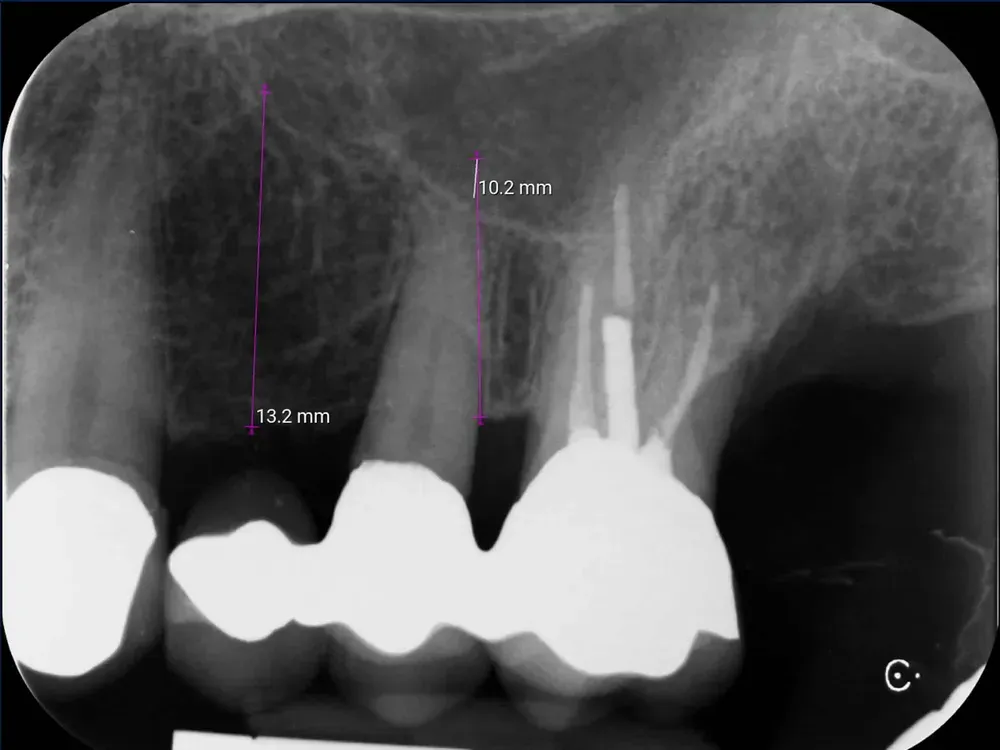

Passati tre mesi, abbiamo effettuato una scansione per realizzare le corone in zirconia. L’ultima radiografia è stata scattata il giorno della consegna delle corone.

L’aumento della densità ossea intorno all’apice dell’impianto in posizione 2.5 è evidente, particolarmente in zona mesiale. In quella zona, la corticale del seno si è sollevata maggiormente.

Rx periapicale alla consegna delle corone in zirconia